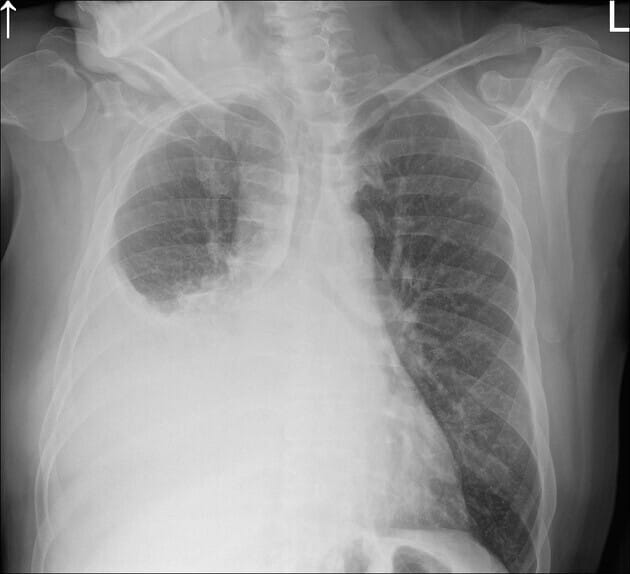

흉부 X-ray

가장 기본적인 검사로, Atelectasis나 Pleural Effusion이 동반될 수 있습니다.

| 중심부 음영(mass) |

| 폐문부 또는 종격동 부위에 종괴성 음영이 관찰될 수 있음 |

| 무기폐 또는 폐렴 유사 소견 |

| 기관지 폐쇄로 인한 폐무기폐(atelectasis) 또는 염증성 음영 가능 |

영상 소견상 특징

- Large right-sided pleural effusion, probably with component of atelectasis as the mediastinum and heart are not displaced contralaterally.